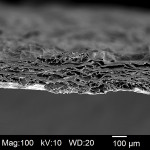

The xenograft barrier used in this case study is a resorbable, highly conformable, biomechanically strong collagen membrane manufactured from purified porcine peritoneum. The peritoneal tissue was purified through a proprietary series of treatments to remove non-collagenous components. After purification, the membrane was gently cross-linked to stabilize the matrix for predictable performance and resorption time. Upon completion of the stabilization step, removal of the cross-linking agent ensured a highly biocompatible membrane. The final product was then cut into various sizes and sterilized by gamma irradiation. The membrane itself is significantly porous, as can be seen in a high-resolution, cross-section scanning electron microscope (SEM) image (Figure 19). This porosity enables absorption of the liquid squeezed from the PRF when it is removed from the tubes and compressed in the perforated metal box. The substantial surface area also enables adsorption of proteins and growth factors onto the collagen itself.